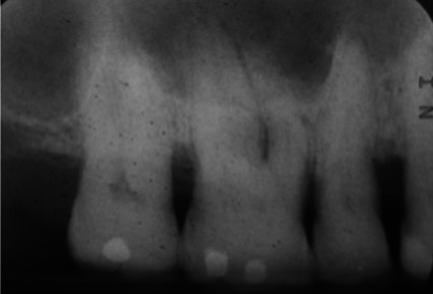

Abstract Image